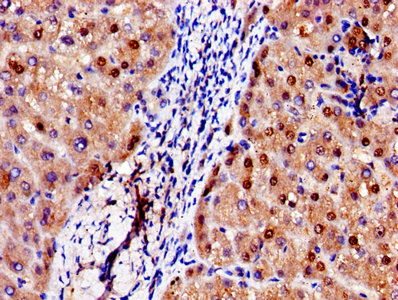

Immunohistochemistry of paraffin-embedded human liver tissue using CSB-PA001311LA01HU at dilution of 1:100